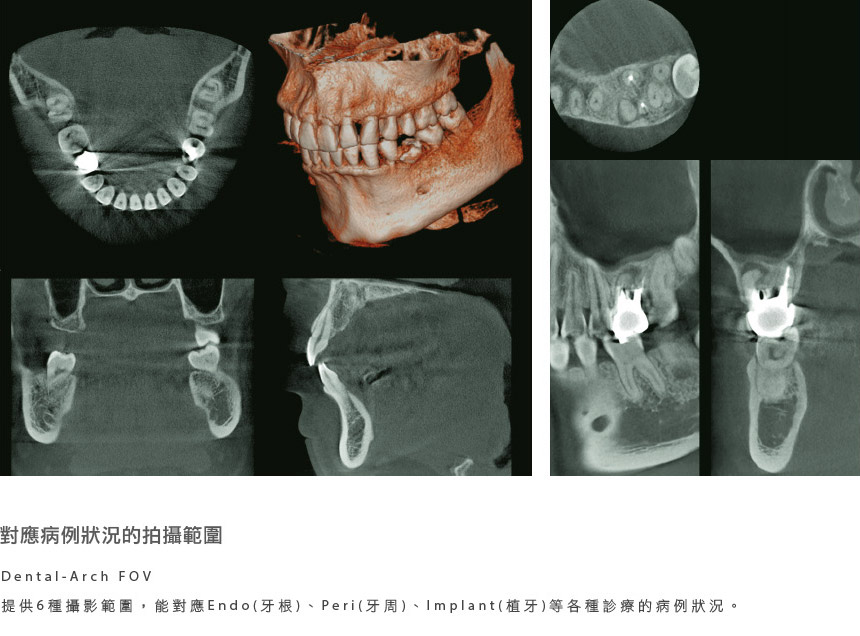

電腦斷層(Computed Tomography, 簡稱CT),意指將影像透過電腦處理後,所顯現出來的3D立體影像「電腦斷層攝影術」。透過電腦斷層,可以完全瞭解患者的口腔狀況,包括︰牙周組織、齒槽骨的寬、高及骨質的結構、牙齒排列、牙齒本身結構、神經血管分布等,提升醫療品質。

但透過3D牙科電腦斷層,可準確判讀全口牙床的位置及齒槽骨情況,並可切換不同的視角來判斷牙床,手術風險相對降低許多。「牙科專用3D電腦斷層(CT)」,透過3D電腦斷層儀器的輔助看診,能幫助醫師與病患達到快速、安全、精準醫療的雙贏局面。